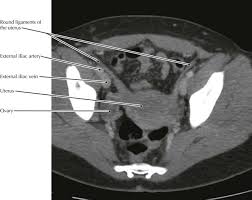

Figure 6.4 • ct scan of pelvis: